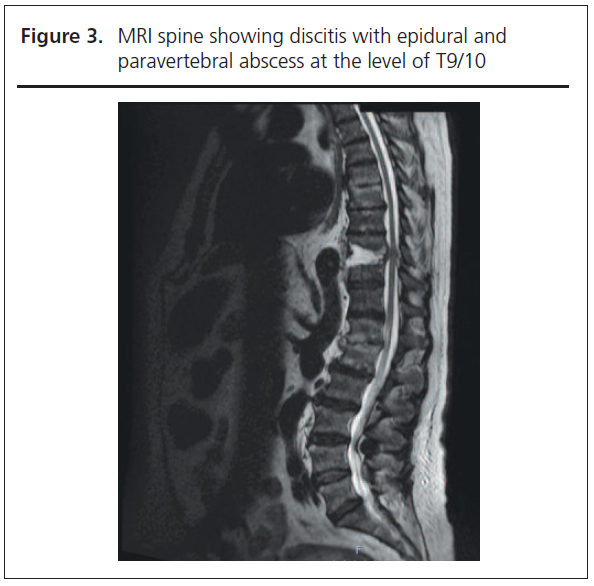

Spinal examination did not reveal any localised tenderness and neurological examination was unremarkable. Blood results on admission showed markedly raised inflammatory markers with a white cell count of 14.9x109/L (neutrophils 12.1x109/L) and a C-reactive protein of 267 mg/L. Plain radiograph of the left foot demonstrated extensive bony destruction of the left hallux (Figure 2), and an MRI scan with contrast confirmed bone marrow oedema extending to the first metatarsal and involving distal tendons of the left hallux, all consistent with osteomyelitis. Time-Resolved Imaging of Contrast Kinetics (TRICKS) suggested significant vascular disease with only the anterior tibial artery being seen, feeding into the dorsalis pedis but not forming a complete plantar arch. There was no evidence of bacteraemia on blood cultures; however, tissue culture from the left hallux isolated coagulase negative Staphylococcus, Streptococcus anginosus and Actinetobacter pittii. Given the ongoing back pain and previous history of spinal osteomyelitis, an MRI scan of the spine was performed which showed discitis with epidural and paravertebral abscess at the level of T9/10 (Figure 3).

Mehta Figure 2